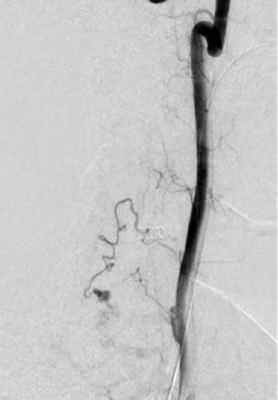

На МРТ шейного отдела позвоночника на вторые сутки после операции определялось уменьшение зоны отека спинного мозга выше и ниже АВМ. Через 3 мес выполнена контрольная селективная спинальная ангиография (рис. 6, а, б) и МРТ шейного отдела позвоночника (рис. 7), по данным которых признаков функционирования АВМ не выявлено. Клинически отмечено улучшение в виде полного регресса верхнего левостороннего монопареза и чувствительных расстройств.

Рис. 6. Контрольная ангиография через 3 мес после операции.

а — селективная ангиография левой позвоночной артерии, артериовенозная мальформация не контрастируется; б — селективная ангиография левого щитошейного ствола, артериовенозная мальформация не контрастируется.